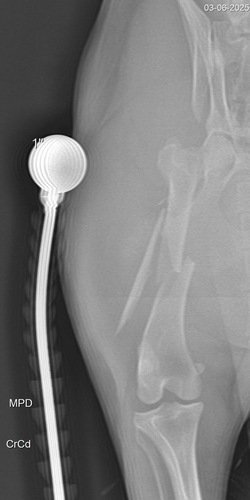

Essa é a Rute, foi atropelada na segunda feira de carnaval, foi resgatada porém não temos o valor para fazer a cirurgia, ela teve múltiplas fraturas e uma bem grave com risco de se tornar exposta!! Precisamos muito da ajuda de todos vocês para que a Rute possa ser operada o mais rápido possível..